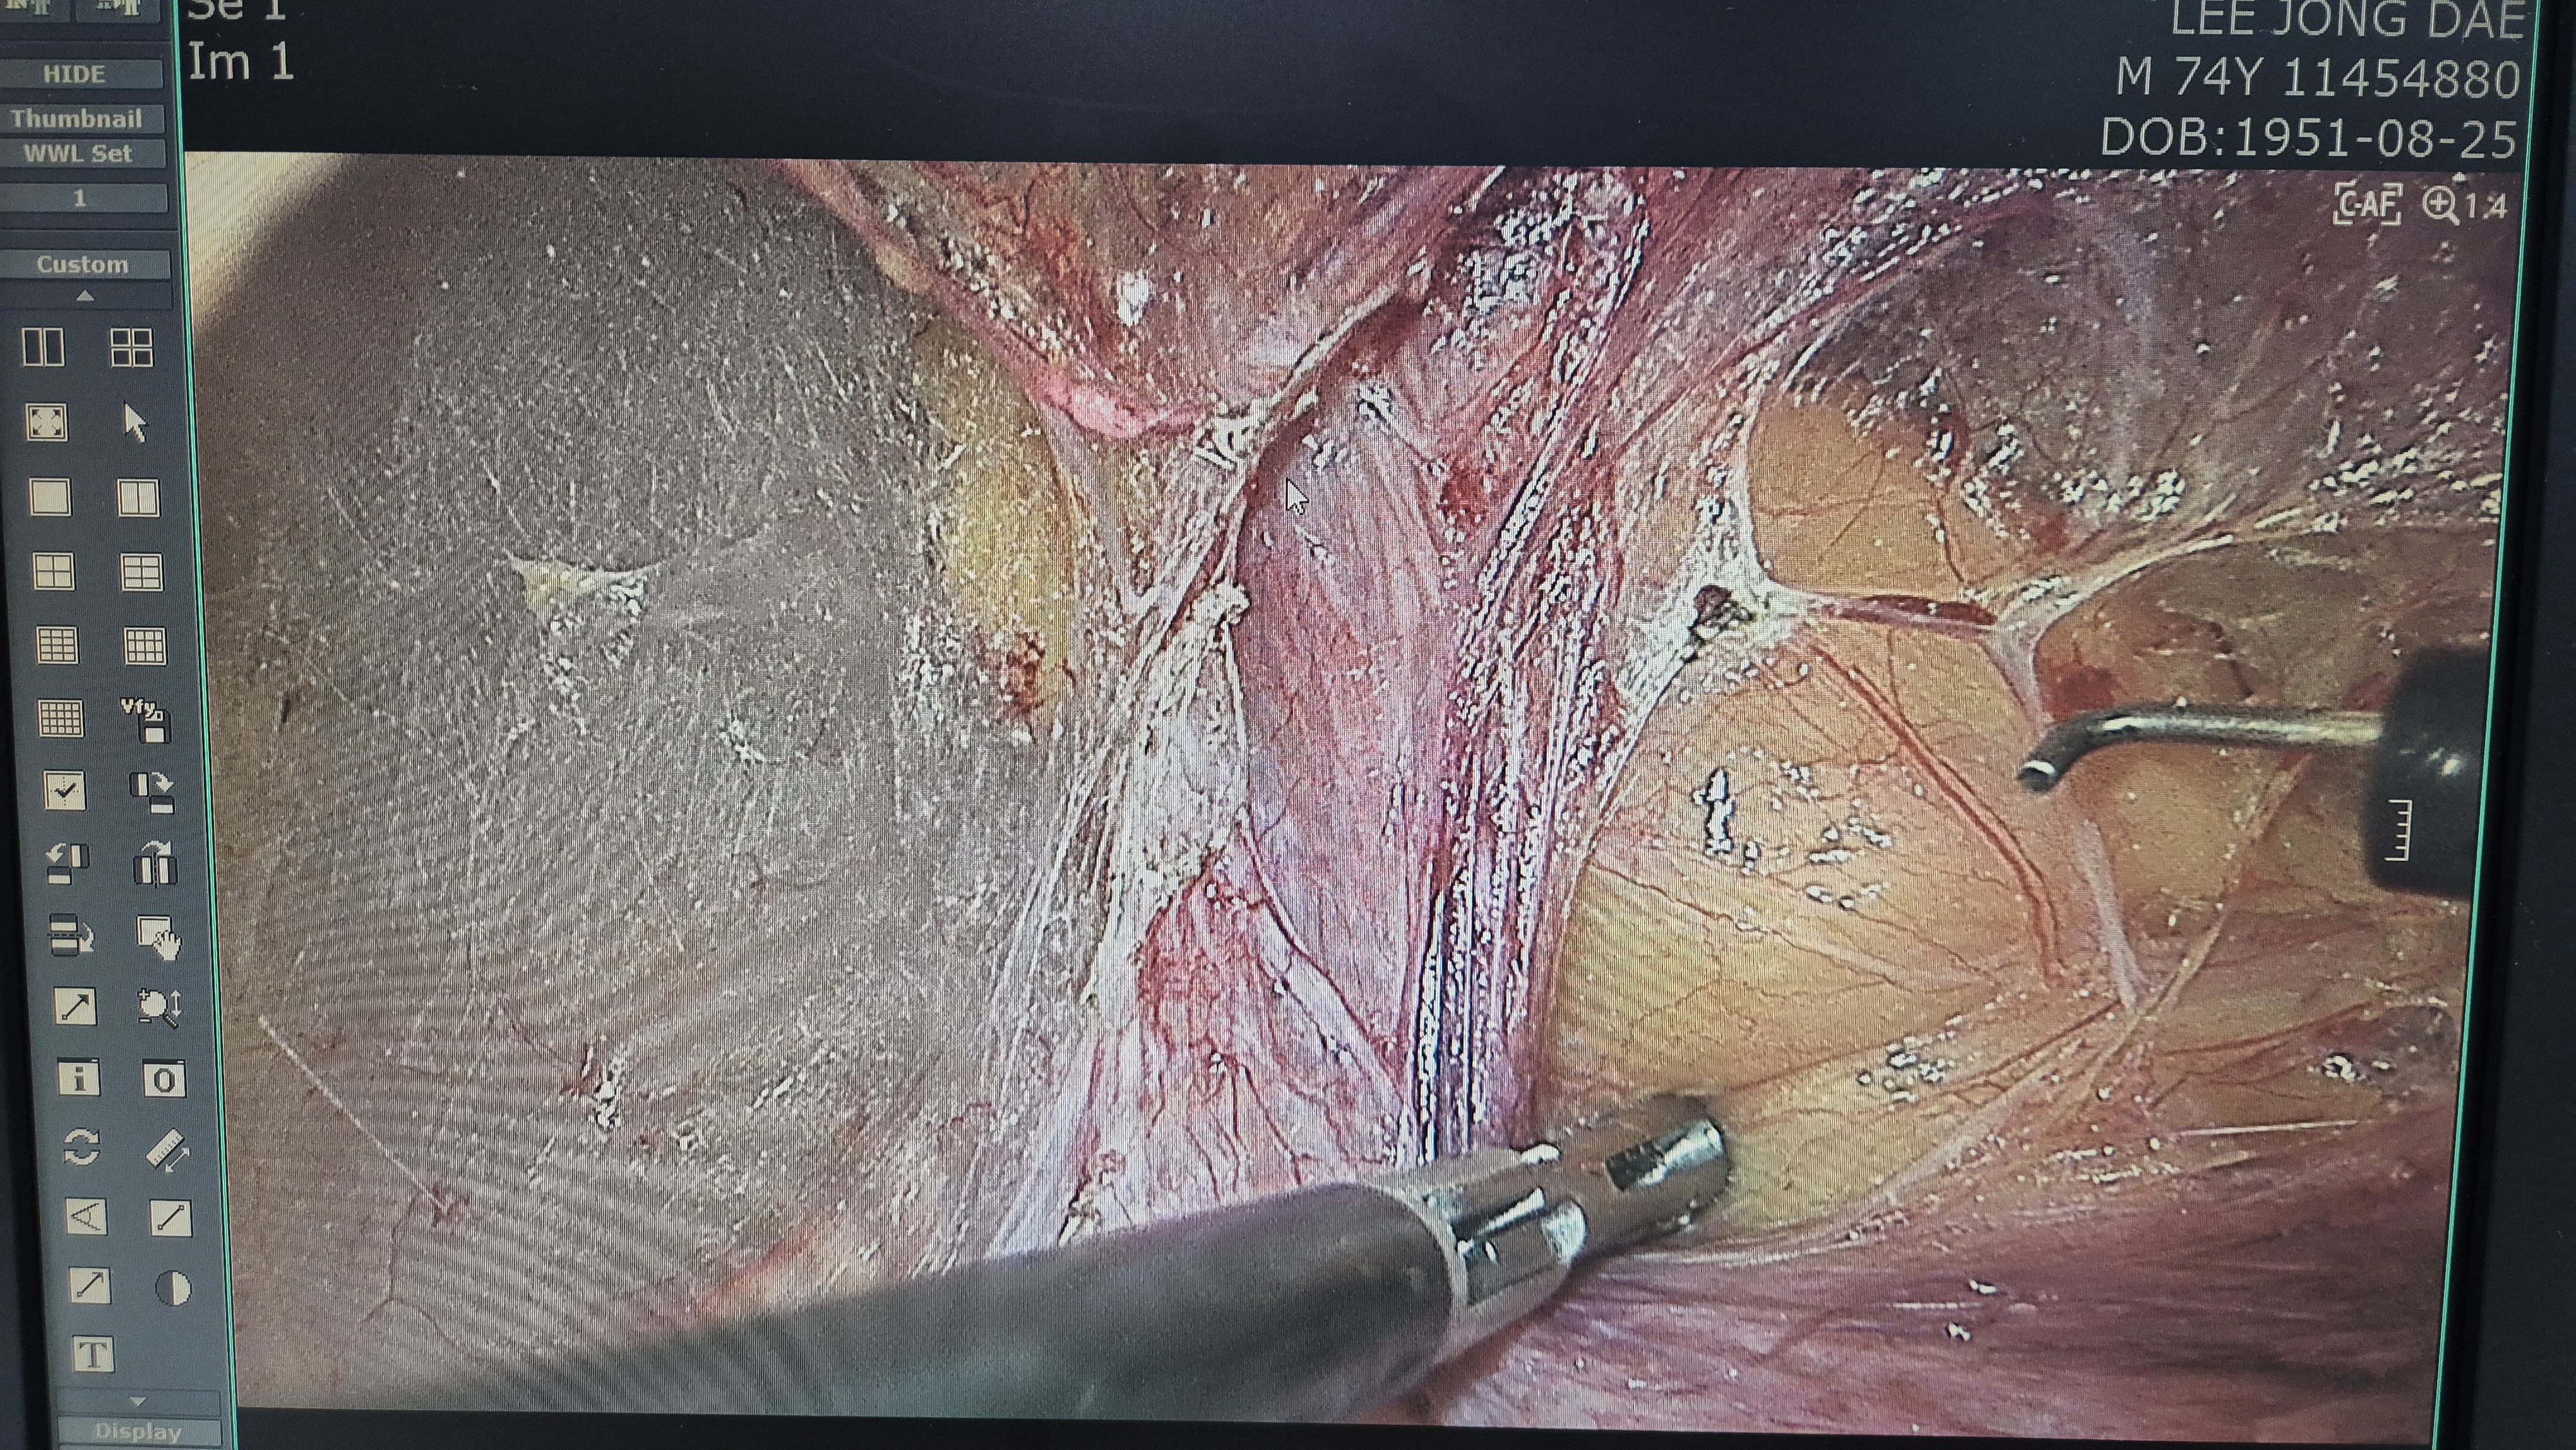

우측 서혜부 종물 주소로 내원하여 초음파 시행후 서혜부 탈장으로 확인되어,

복강경 탈장교정술을 시행했습니다.

탈장 확인후.

박리.

메쉬로 고정.

수술은 20분 걸렸습니다.